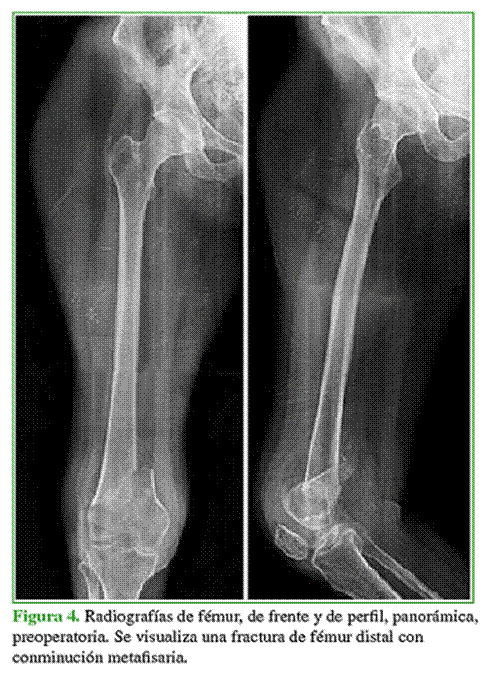

En todos los pacientes, se observó la consolidación radiográfica a los seis meses de la cirugía definitiva. Dos pacientes de la muestra tenían, en el momento de la osteosíntesis, defectos metafisarios que fueron resueltos con espaciadores de cemento y antibiótico, por lo que requirieron una nueva intervención con la colocación de injerto de banco. En estos casos, la carga se retrasó seis semanas, momento en el cual se realizó el segundo tiempo quirúrgico que consistió en el retiro del espaciador y el relleno del defecto con injerto óseo cadavérico. Nuevamente, se retrasó la carga seis semanas, y se logró la consolidación en ambos casos. En el resto de los pacientes, se inició un protocolo de carga progresiva que consistió en carga parcial por tres semanas y luego carga completa. Ninguno tuvo una lesión vasculonerviosa asociada (Figuras 3-6).

El puntaje promedio de dolor posoperatorio luego de la consolidación de la fractura fue 3. El paciente con cuadriplejia no fue evaluado en este aspecto (Tabla 2). El seguimiento radiográfico se realizó en el posoperatorio inmediato, a las 3 y 6 semanas, y a los 3, 6, 12, 18 y 24 meses. En la Tabla 3, se describen los resultados funcionales según el puntaje KOOS.6,7 La mediana de seguimiento fue de 24 meses (rango 6-36).